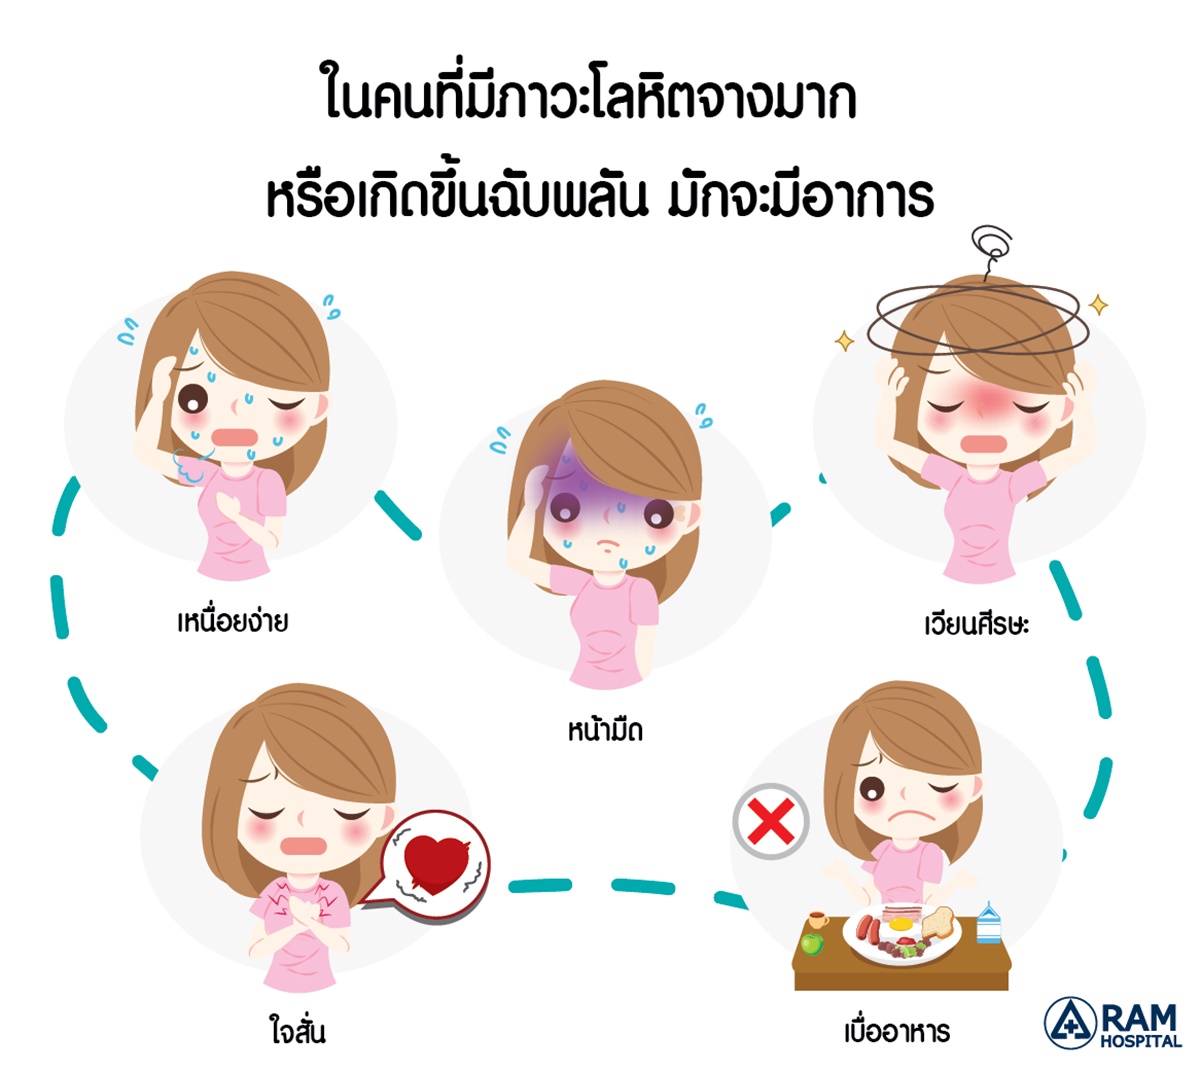

อ่อนเพลียเรื้อรังระวังภาวะโลหิตจาง จากการขาดธาตุเหล็ก – Pantip รูประบบร่างกายมนุษย์เวกเตอร์ของผู้หญิง PNG , คลิปอาร์ต, ร่างกายผู้หญิง …